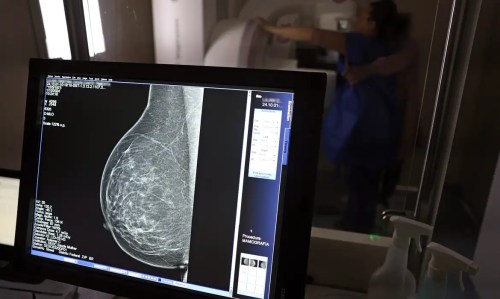

“A importância é conscientizar as pessoas da importância de examinar as suas mamas, pelo menos anualmente, ou fazer o autoexame ou utilizar formas de diagnósticos automatizadas de imagens com profissionais especialistas, porque o câncer de mama é o que mais mata no mundo. É a primeira maior causa de morte de mulheres. E hoje, a gente tem um aumento significativo da incidência de câncer de mama em mulheres mais jovens”, afirma a doutora.

Um dos principais sintomas da doença é a alteração da mama, com a presença de nódulos, inflamações e até a saída de líquido sanguinolento pelo mamilo. Além dos sinais, alguns fatores de risco influenciam o desenvolvimento do câncer de mama como idade, quantidade de partos, aleitamento, genética familiar e histórico de doença na família. A doutora Ângela comenta como estes fatores são detectados na consulta médica.

Uma das principais vertentes do Outubro Rosa é a importância do diagnóstico precoce para aumentar as chances de cura. Para esclarecer este fato, a doutora Ângela fala sobre a relação entre a detecção rápida com as altas probabilidades de recuperação.